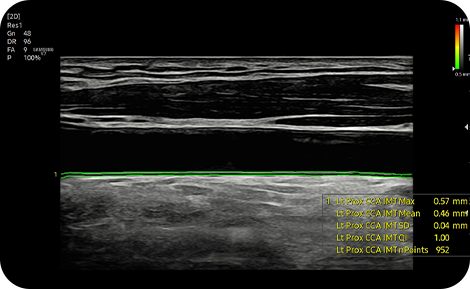

Measure IMT in one click

AutoIMT+ is a screening tool to analyze a patient’s potential risk of cardiovascular disease. It allows easy intima-media thickness measurement of both the anterior and posterior wall of the common carotid by the click of a button.

cardiovascular ultrasound tech : AutoIMT+

ArterialAnalysis™ detects functional changes of vessels, providing measurement values such as the stiffness, intima-media thickness and pulse wave velocity of the common carotid artery.

medical solution : ArterialAnalysis™